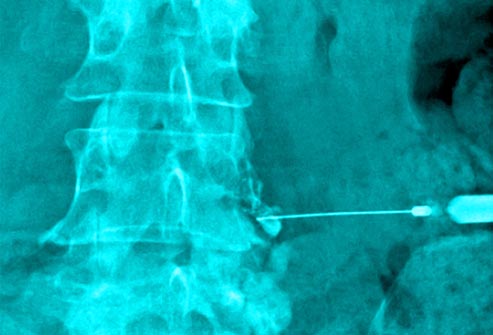

Injections

If simpler therapies and medications aren't helping, your doctor may recommend injections to the back. One procedure, called a nerve root block, targets irritated nerves. Injections for back pain usually contain steroid medication.Surgery